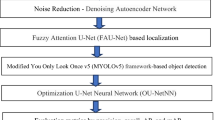

Detecting cardiac abnormalities between 14 and 28 weeks of gestation with an apical four-chamber view is a difficult undertaking. Several unfavorable factors can prevent such detection, such as the fetal heart’s relatively small size, unclear appearances in anatomical structures (e.g., shadows), and incomplete tissue boundaries. Cardiac defects without segmentation are not always straightforward to detect, so using only segmentation cannot produce defect interpretation. This paper proposes an improved semantic segmentation approach that uses a region proposal network for septal defect detection and combines two processes: contour segmentation with U-Net architecture and defect detection with Faster-RCNN architecture. The model is trained using 764 ultrasound images that include three abnormal conditions (i.e., atrial septal defect, ventricular septal defect, and atrioventricular septal defect) and normal conditions from an apical four-chamber view. The proposed model produces a satisfactory mean intersection over union, mean average precision, and dice similarity component metrics of about 75%, 87.80%, and 96.37%, respectively. Furthermore, the proposed model has also been validated on 71 unseen images in normal conditions and produces 100% sensitivity, which means that all normal conditions without septal defects can be detected effectively. The developed model has the potential to identify the fetal heart in normal and pathological settings accurately. The developed deep learning model's practical use in identifying congenital heart disorders has substantial future promise.